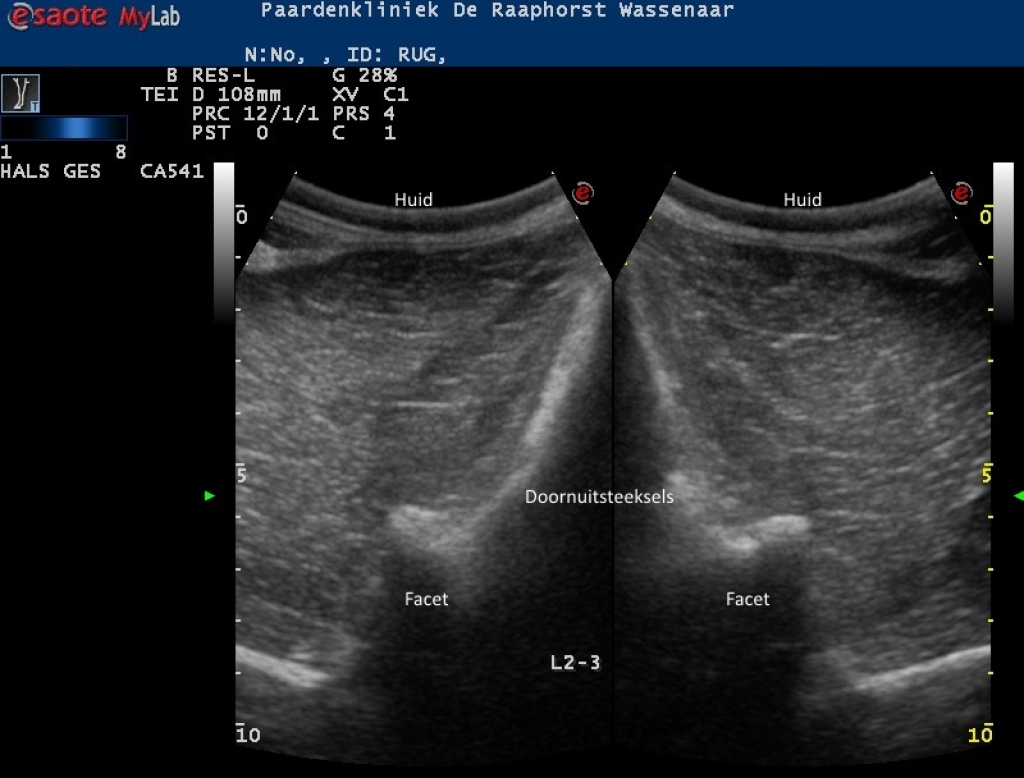

Rechts: Echografische beeld van normale facetgewricht van de lendenwervels

Echografische beeld van normale facetgewricht van de lendenwervels